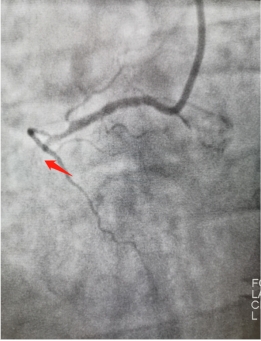

此刻,在手术台的另一边,胸痛中心的张松和赵洪伟两位医生,在高度紧张的氛围下,争分夺秒的为患者进行了冠脉造影检查,结果显示患者为右冠状动脉闭塞,血流完全消失。两位医生当机立断,立刻为患者实施血栓抽吸及球囊扩张术,期间患者又再次反复发作心室颤动,整个身体极度扭曲、不受控制,两位医生凭借过硬的心理素质及娴熟的手术技术,顺利为患者开通了血管并置入一枚支架,整个过程不超过五分钟。随着闭塞血管血流再通,患者逐渐恢复了意识,胸痛症状得到明显缓解,心室颤动波形也随之消失,患者术后安全转入CCU病房监护治疗。

右冠状动脉支架前后对比